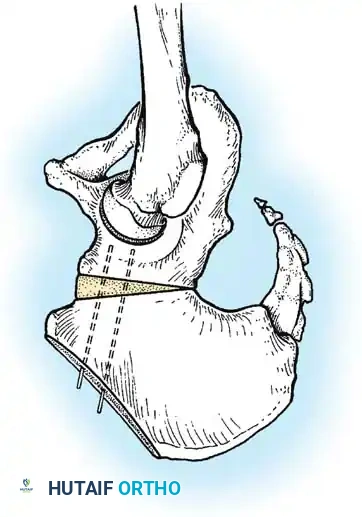

Anterior Approach (Smith-Petersen):

1. Incision: "Bikini" incision below the iliac crest.

2. Interval: Develop the plane between the tensor fasciae latae (superior gluteal nerve) and the sartorius (femoral nerve).

3. Deep Dissection: Detach the rectus femoris from the AIIS. Isolate and release the iliopsoas tendon at the pelvic brim to relieve the hourglass constriction of the capsule.

4. Capsulotomy: A T-shaped or I-shaped capsulotomy is performed parallel to the acetabular margin.

5. Joint Clearance: Excise the ligamentum teres, clear the pulvinar, and incise the transverse acetabular ligament inferiorly. Never excise the limbus, as it is critical for future acetabular growth; radial incisions may be made if it is severely inverted.

6. Capsulorrhaphy: Following concentric reduction, the redundant capsule is advanced superiorly and laterally to stabilize the joint.

Intraoperative view of the anterior approach to the hip, demonstrating capsulotomy and exposure of the dysplastic joint.